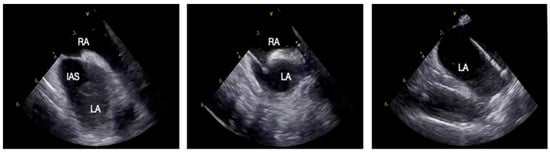

Intracardiac Echocardiography in Structural Heart Interventions: A Comprehensive Overview

by Francesco Leuzzi, Ciro Formisano, Enrico Cerrato, Antongiulio Maione, Tiziana Attisano, Francesco Meucci, Michele Ciccarelli, Carmine Vecchione, Gennaro Galasso and Francesca Maria Di Muro

Intracardiac echocardiography (ICE) is increasingly recognized as a valuable imaging modality in structural heart interventions, offering high-resolution, real-time visualization from within the cardiac chambers. Originally developed for electrophysiologic procedures, ICE has expanded its use across a broad spectrum of structural interventions, including atrial [...] Read more.

Intracardiac echocardiography (ICE) is increasingly recognized as a valuable imaging modality in structural heart interventions, offering high-resolution, real-time visualization from within the cardiac chambers. Originally developed for electrophysiologic procedures, ICE has expanded its use across a broad spectrum of structural interventions, including atrial septal defect (ASD) and patent foramen ovale (PFO) closure, left atrial appendage occlusion (LAAO), transseptal puncture guidance, transcatheter edge-to-edge repair (TEER), balloon mitral valvuloplasty, and both mitral and tricuspid valve therapies. This review outlines the current role and technical principles of ICE, with an emphasis on catheter design, image acquisition protocols, and the emerging potential of 3D ICE. Comparisons with transesophageal echocardiography (TEE) and fluoroscopy are discussed, highlighting ICE’s ability to support minimally invasive, sedation-sparing procedures while maintaining procedural precision. We provide a focused analysis of ICE-guided applications in specific clinical scenarios, emphasizing its role in anatomical assessment, device navigation, and intra-procedural monitoring. Data from recent clinical studies and registries are reviewed to assess safety, feasibility, and outcomes. Practical considerations including operator learning curve, workflow integration, and limitations such as cost and field of view are also addressed. Lastly, we explore future directions including advanced 3D imaging, fusion imaging, artificial intelligence integration, and robotic catheter systems. Full article